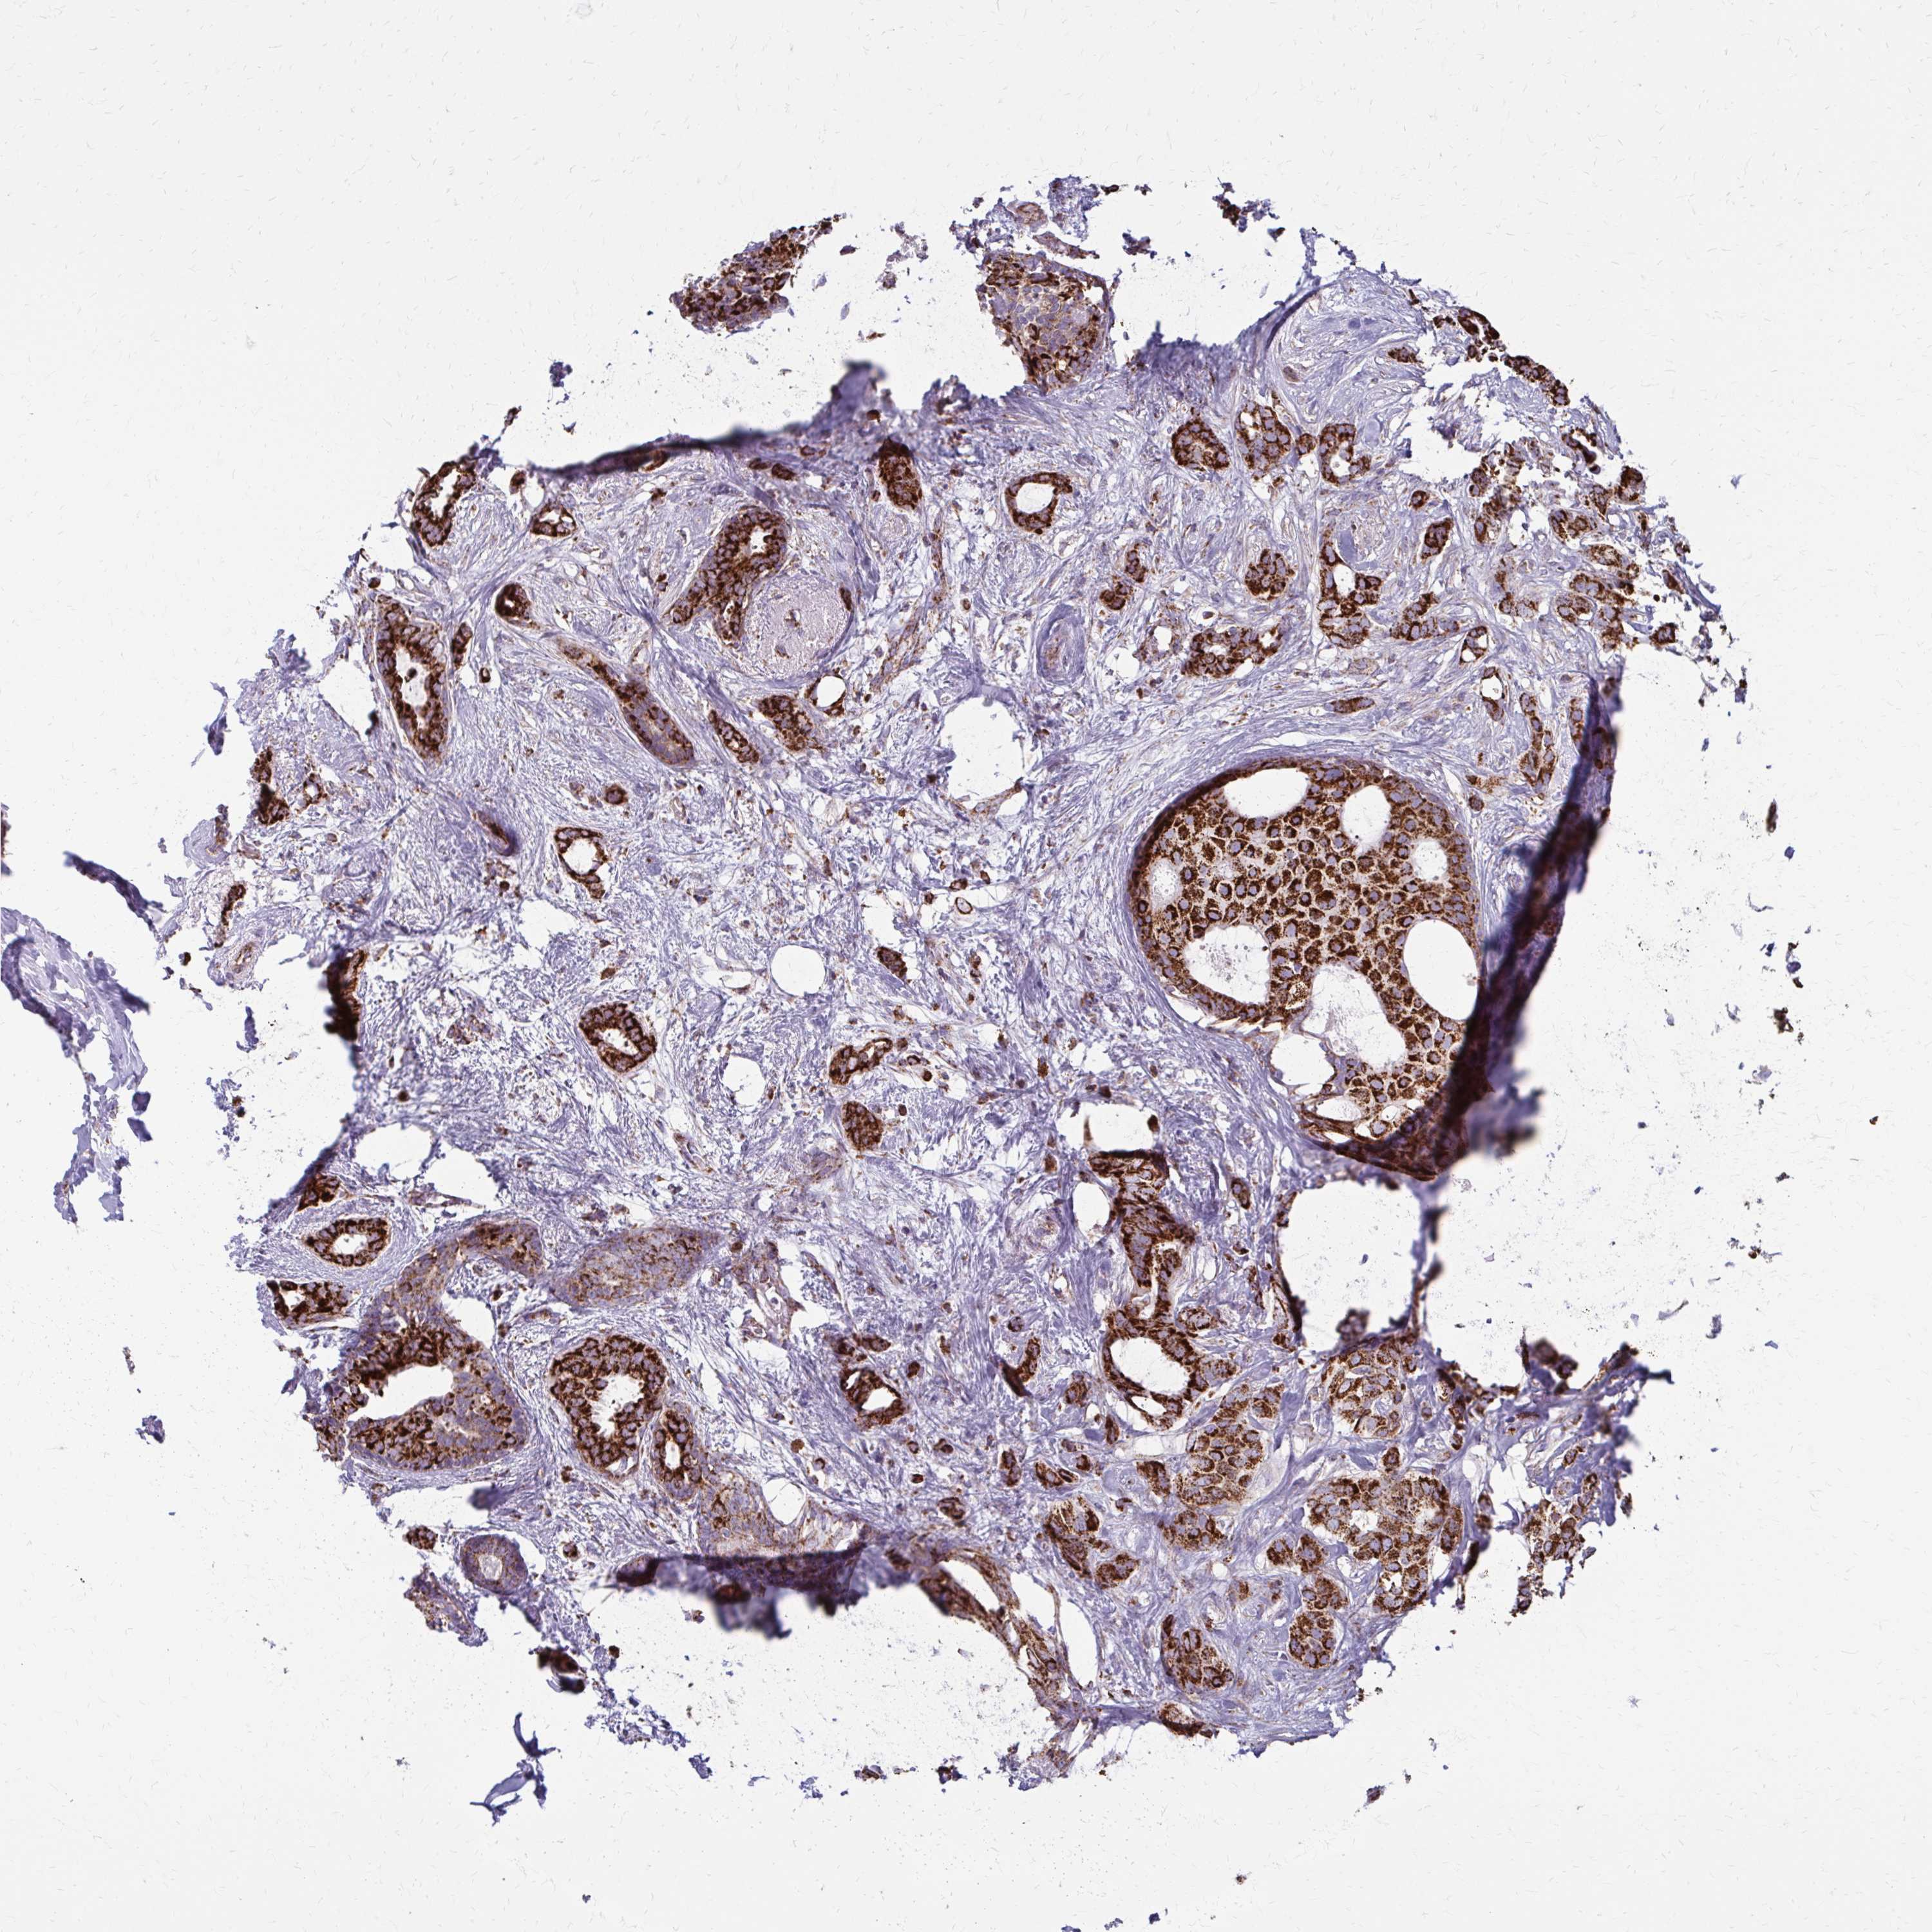

CANCER BREAST CANCER Show tissue menu

BRCA TCGA BRCA VALIDATION PROTEIN EXPRESSION